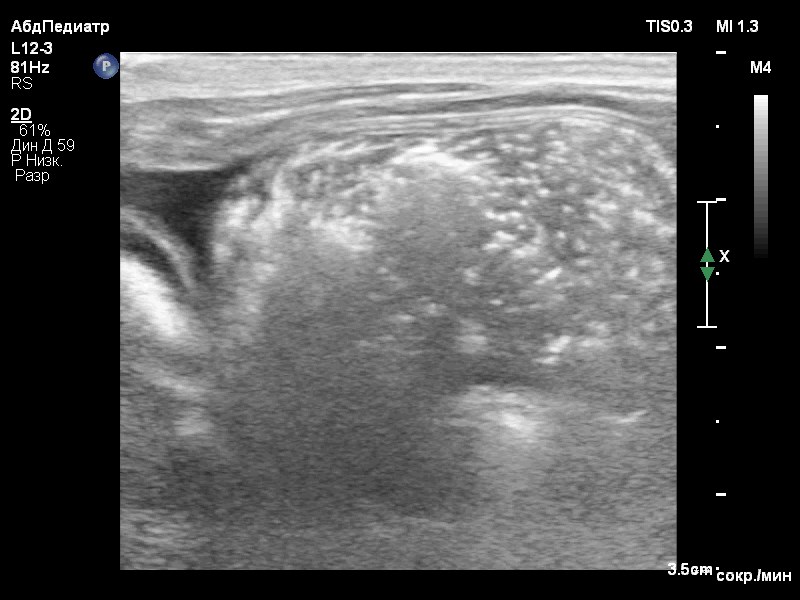

Были проведены лабораторные исследования крови, включающие биохимический и клинический анализы. В результате проведения биохимического анализа было выявлено умеренное повышение гепатоцеллюлярных ферментов (табл. 1), в то время как результат клинического анализа показал легкую анемию без признаков регенерации. Дополнительно были измерены уровни желчных кислот методом парных проб (до и после кормления). Результаты показали выраженное повышение, что свидетельствует о синтетической дисфункции печени (табл. 2). Уровень глюкозы в крови составил 3,4 ммоль/л при норме 3,5–6,1 ммоль/л, что указывает на наличие легкого уровня гипогликемии.Ультразвуковое исследование органов брюшной полости выявило признаки микрогепатии, нефролитиаза, уролитиаза и асцита (скопление жидкости в брюшной полости) в небольшом количестве (до 2 мм на просвет; фото 1).